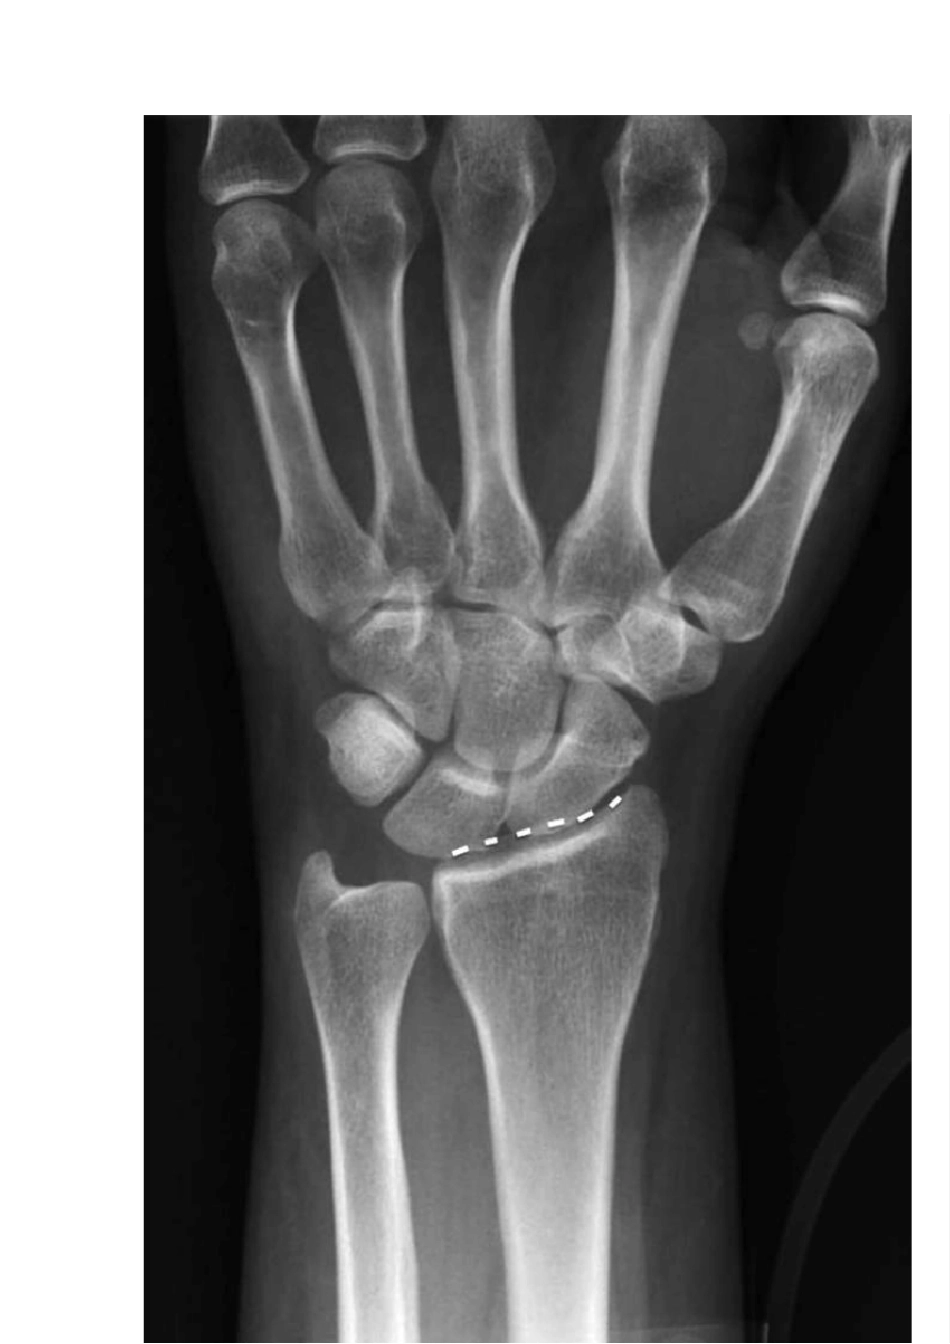

JAAOS 综述:桡骨远端骨折治疗争议 桡骨远端骨折在日常诊疗过程中较为常见,国内现在的治疗趋势是对能耐受手术的中青年患者基本会建议手术;而对腕关节功能要求较低的患者,则手术或者非手术治疗基本接近。 尽管笔者对上述观察结果的总结并不一定正确,但也从侧面证明一个问题,即现阶段桡骨远端骨折治疗仍争议重重。在 2014 年 9 月份的美国 JAAOS 杂志上刊登了目前桡骨远端相关的争议点,包括诊断,影像学评估,治疗和预后等方面,现将中文翻译版呈现给各位,以供在临床实践中参考。 文末会给各位推荐数篇桡骨远端治疗的相关指南和病例介绍,是早先丁香园骨科频道译者(@第五十七回 )对 AAOS 桡骨远端骨折治疗指南的解读,欢迎各位点击阅读。 桡骨骨折相关的问题,包括桡骨骨折评估,诊断,治疗及功能预后的评估等极富争议。各种影像学检查手段在评估桡骨骨折中的准确性均未得到确实有效的证实。此外,桡骨远端的分类方法多样,大部分分类方法在不同观察者间及同一观察者内的可靠性也存在较多疑问。 非手术治疗桡骨远端的主要争议点在于骨折的复位,麻醉的使用,骨折的制动时间,前臂在骨折愈合过程中的位置等。手术治疗桡骨远端骨折的争议点包括手术指征,术后出现腕管综合征需要再次手术减压,骨折固定的方法,骨折固定是否需要加强。桡骨骨折术后的康复策略,用药,物理锻炼方法等也存在较多争议。目前临床上对桡骨远端骨折的临床功能预后使用何种标准评估尚无统一的意见。上述所有争议内容后期需要更多的临床研究进行进一步的评估。 桡骨远端骨折在临床中较为常见,其年发生数量为 60 万例。其发病年龄呈现双峰的特点,即以高能量损伤的年轻人和低能量损伤的老年人为主体。2007 年,美国桡骨远端骨折的医疗花费接近 1.7 亿美元。 对桡骨骨折采取合适的治疗方案要求临床医生准确的评估骨折形态,诊断,治疗,并熟悉术后功能恢复评估方法。桡骨骨折诊断,治疗,术后评估等均存在较多争议。2009 年美国 AAOS 协会发布了第一版的桡骨远端骨折治疗指南,但是上述指南的临床证据并不充分。 争议点:骨折评估 临床上有很多方法可以评估桡骨远端骨折。前后位,侧位,斜位 X 片等可以评估桡骨的倾斜,长度和掌倾角(图 1)。前后位 X 片清晰的桡骨远侧边缘和侧位片上清晰的泪滴样桡骨远端是正常的解剖学表现。在前后位 X 片上,桡骨远端背侧边缘投影要超过桡骨近端骨皮质约 3-5m m 。侧位片时,泪滴点的切线和...